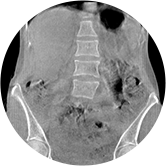

三维脊柱应用

精准诊断

手术方案规划

术后随访

• 脊柱评估

传统方法都是在二维平面,依靠棘突或椎弓根相对于椎体的偏移来评估脊柱侧凸。WR-3D可以更精准评估脊柱侧凸,制定手术方案,可以更直观地显示和量化椎体的平移和轴向旋转,术后评估更准确客观。